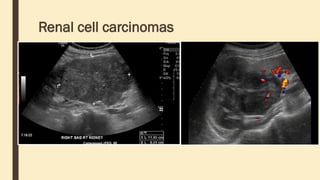

Renal cell carcinomas

Ultrasound ■ uncomplicated renalcyst – well-marginated anechoic lesion with thin walls – a few thin septa may be present (5% of cysts) – posterior acoustic enhancement may be present, although this finding is non-specific and also may not be seen with smaller cysts – a small amount of intracystic hemorrhage/debris may be present and may require further evaluation (5% of cysts) ■ complicated cyst – cystic lesions with thickened or irregular walls or septa are suspicious for renal cell carcinoma and warrant further work up – vascularity of the septa on color or spectral Doppler is suspicious for renal cell carcinoma